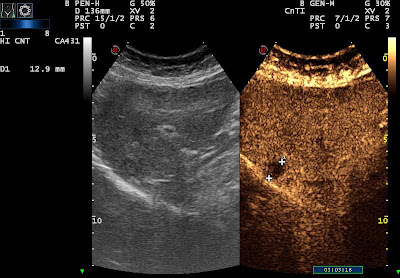

| third met |